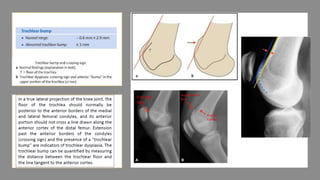

metaphyseal-diaphyseal angle isthe angle created by the intersection of a line through the transverse plane of the proximal tibial metaphysis with a line perpendicular to the long axis of the tibial diaphysis Blounts EMA > 20* MDA > 11*